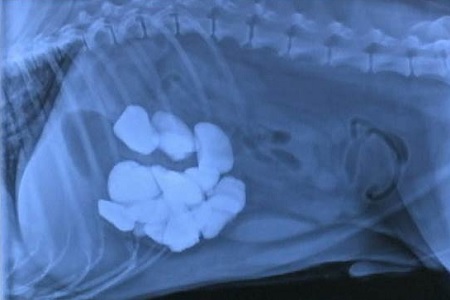

L’ingestione di oggetti o di materiale non alimentare è un comportamento che può diventare davvero molto pericoloso. In sostanza, gli oggetti tendono a provocare le classiche conseguenze legate alla presenza di corpi estranei nello stomaco o nell’intestino. Se invece l’animale tende ad ingerire sostanze più naturali, come fango, terriccio o lettiera, può andare incontro ad altri tipi di problemi. Vediamo quali sono i principali effetti dannosi della pica:

Costipazione e blocco intestinale: un oggetto o un agglomerato di lettiera possono rimanere incastrati a lungo nell’intestino, impedendo al cibo e alle feci di passare. Un’occlusione intestinale è un problema molto grave, che spesso richiede un intervento chirurgico d’urgenza. Ancora più particolare è il rischio legato all’ingestione di gomitoli di lana, spago e lacci: questi possono “agganciarsi” in un punto dell’intestino, che finisce così per attorcigliarsi su se stesso;